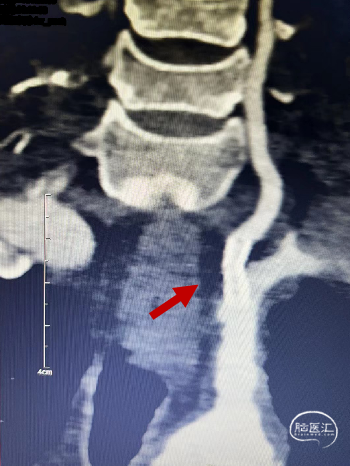

CTA提示:右侧椎动脉纤细,左侧椎动脉V1、V4段纤细。

左侧椎动脉开口重度狭窄,前向血流缓慢,V4闭塞。

保留微导丝、Guiding回撤到锁骨下,观察椎动脉开口:椎动脉开口无法维持。拟行椎动脉开口支架成形术,选用4mm*15mm Bridge椎动脉雷帕霉素靶向洗脱支架。

术后CTA:Bridge药物支架形态良好,前向血流良好。

术后半年CTA:Bridge支架形态及贴壁良好,前向血流正常。